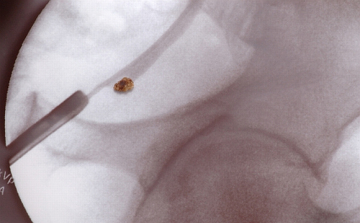

A vesekő tünetei és kezelése